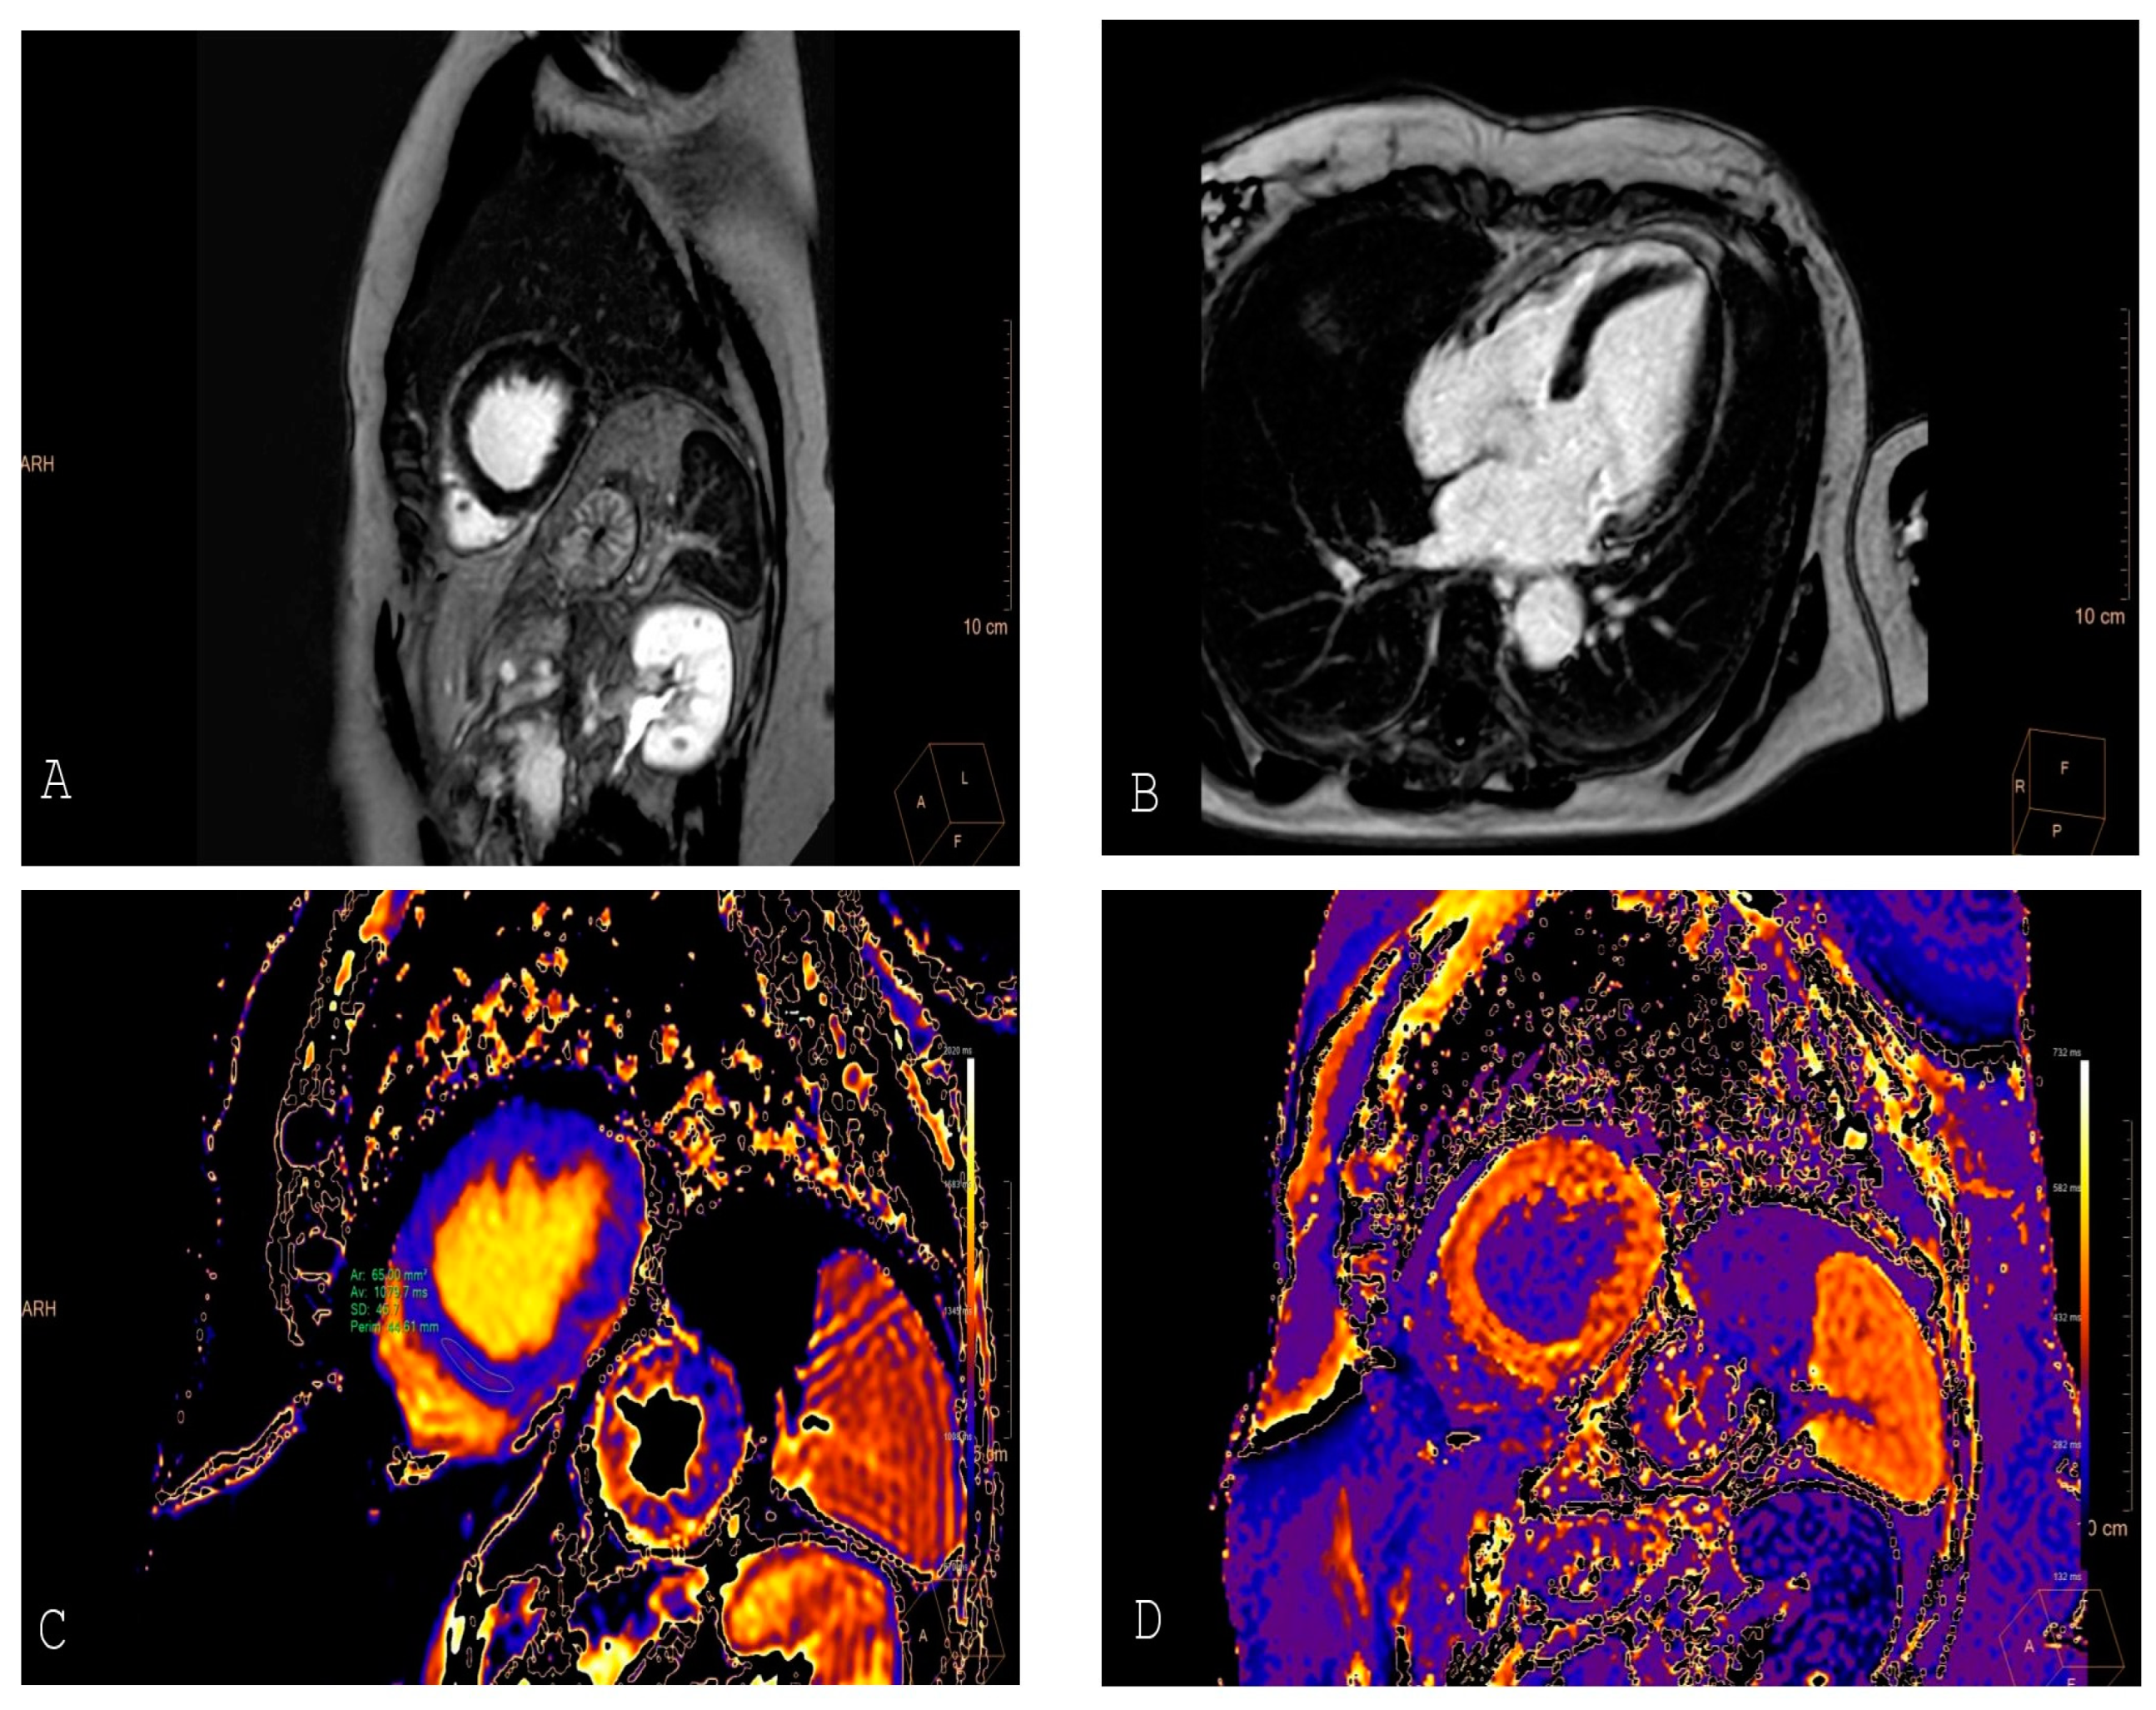

4. Cardiac Magnetic Resonance (CMR) Imaging